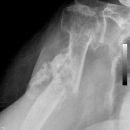

Dislozierte subcapitale Fraktur mit Tbc majus